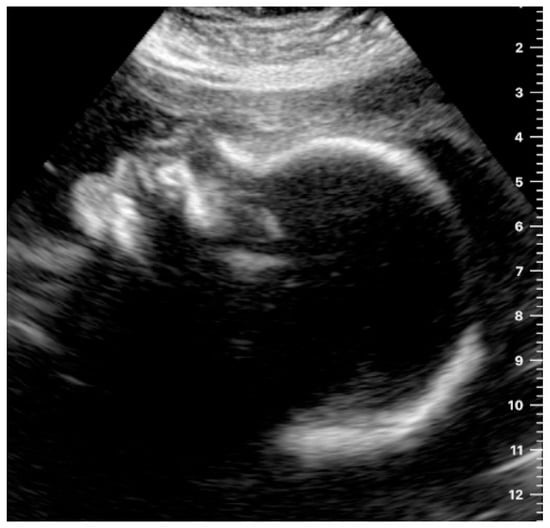

The heartbeat was correctly captured by more than half of the participants (n = 24, 52.2%; Table 3) (Figure 2a,b).

Figure 2.

(a) Example of an image obtained by a study participant in cohort A, showing the heartbeat (satisfactory presentation). (b) Example of an image obtained by a study participant in cohort B, showing the heartbeat (satisfactory presentation).